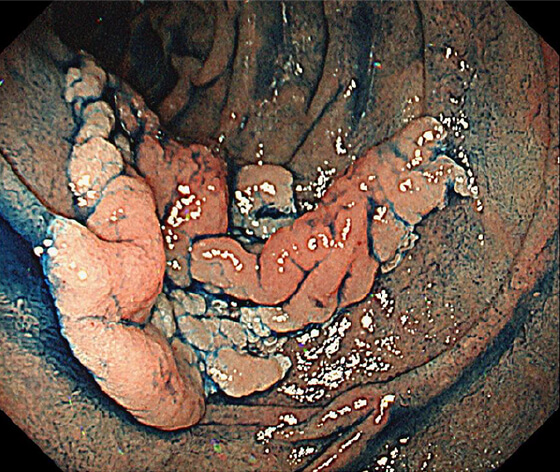

放射線療法後の遺残再発食道癌に対する光線力学的療法(PDT)も行っており、PDTの実施可能施設は九州で4施設のみ、長崎県内では当院が唯一の実施施設となっています。

PDT